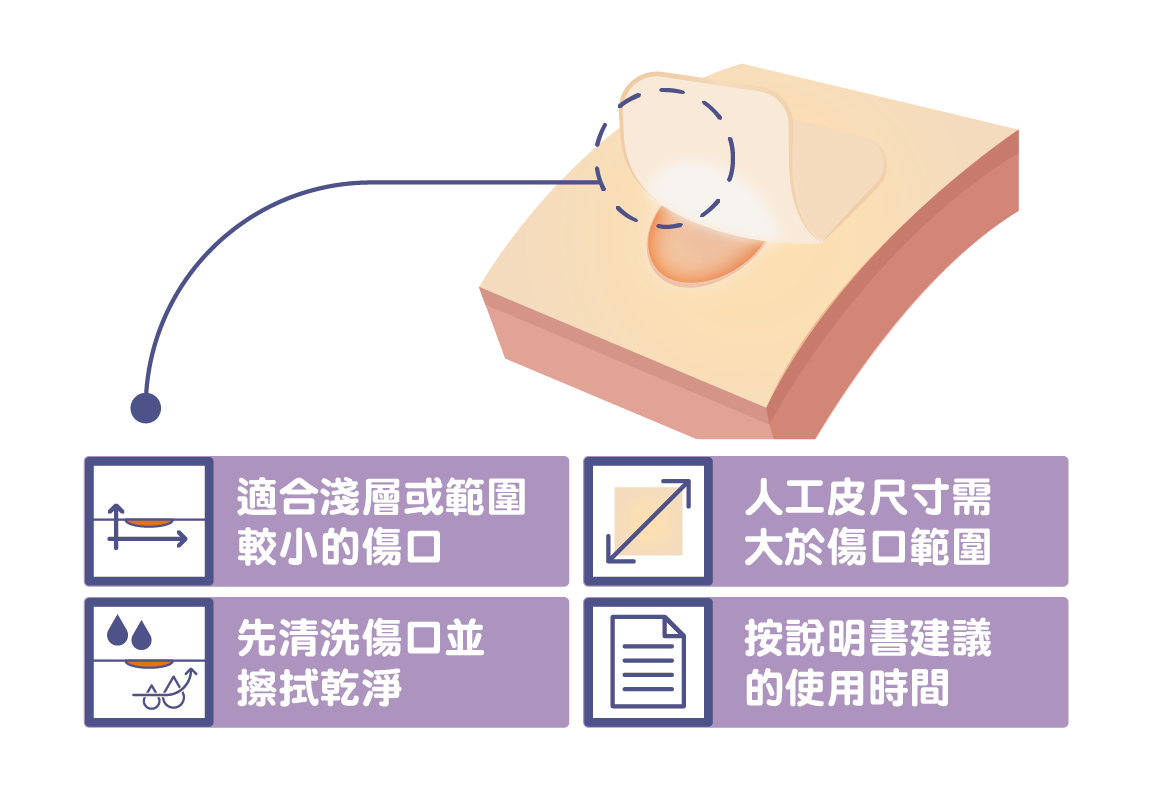

用對人工皮,傷口神救援!

您家裡是否有個活潑的孩子,常常摔跤跌傷、造成傷口?此時,很多父母會想到「人工皮」。所謂的人工皮是一種親水性敷料,適當使用人工皮覆蓋在傷口上,能維持傷口的濕潤並吸收傷口的分泌物,有助傷口修復。但是,食品藥物管理署(下簡稱食藥署)提醒,如果沒有選對、貼對人工皮,反而容易造成傷口感染。

人工皮貼多久?什麼時候該換?看這個來判定

受了傷不想留下疤痕,大部分的人都會選擇貼「人工皮」,促進傷口癒合。但常聽到人說,「人工皮」不用每天更換、貼越久越好?食藥署表示,一般而言,人工皮可黏貼2~3天,視傷口滲液狀況再進行更換,建議不可使用超過7天。